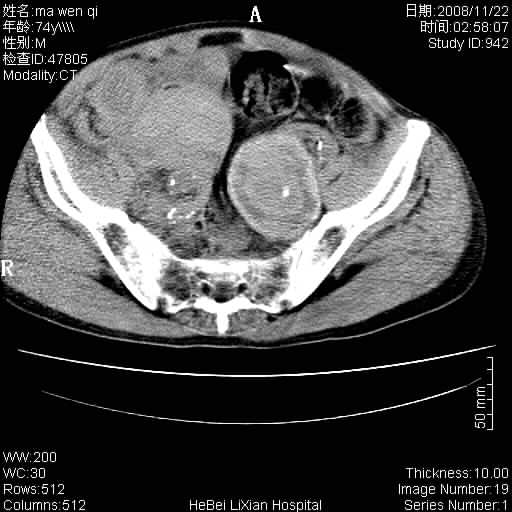

患者男 74岁.突然昏迷,休克6小时.血压70/30,头颅ct未见异常,既往体健.

补充病史,保留导尿10小时,尿袋内只有少许尿液,患者于住院后15小时后去世.

腹主动脉、双侧髂动脉夹层动脉瘤破裂出血进入腹腔。

1)考虑双侧髂动脉瘤并右侧动脉瘤破裂出血,右侧腹膜后及腹腔积血。2)双侧腹股沟疝。

1)考虑,腹主动脉、双侧髂动脉夹层动脉瘤破裂伴右侧腹膜后及腹腔积血。2)双侧腹股沟疝。

1)考虑胸、腹主动脉、双侧髂动脉瘤并右侧动脉瘤破裂出血,右侧腹膜后及腹腔积血。2)双侧腹股沟疝。

腹主动脉、双侧髂动脉夹层动脉瘤破裂。